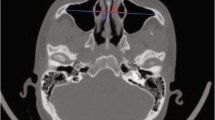

The horizontal line of the supraorbital margin in the coronal view was used as the transverse line (line b), and the vertical line was made at the supraorbital (neurovascular bundle) notch (line a). The development status of the frontal sinus was classified by the four-quadrant method [5]. The pneumatization of the frontal sinus within the lower quadrant was considered as under-development. The pneumatization of the frontal sinus range from the upper to the inner quadrant was considered as moderate development. The type with pneumatization extending to the outer upper quadrant was considered as well developed. If no pneumatized frontal sinus was present in the frontal bone, it was considered as undeveloped type (Fig. 1A). According to the IFAC classification criteria [21], three otolaryngologists familiar with the IFAC system independently read all CT scans, evaluated the presence and number of air cells around the frontal recess, and calculated the incidence of each type of air cell. Responsible cells (RC) were defined as those whose extent exceeded 50% of the frontal recess and might affect the drainage of the frontal sinus when the film was continuously read in the coronal and sagittal views.

Three-dimensional reconstruction